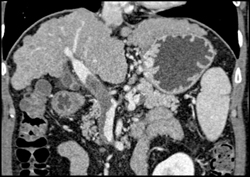

Diagnosis

Multiple Stenosis in Superficial Femoral Aas